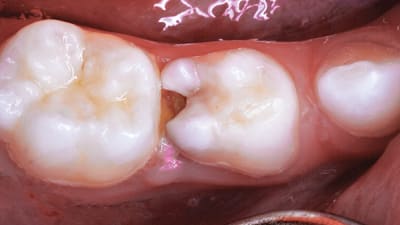

Restorative Restorative Direct Diagnosis and Treatment Planning Creating Predictable Composite Contacts By Parag R. Kachalia, DDS November 01, 2019 10 min read